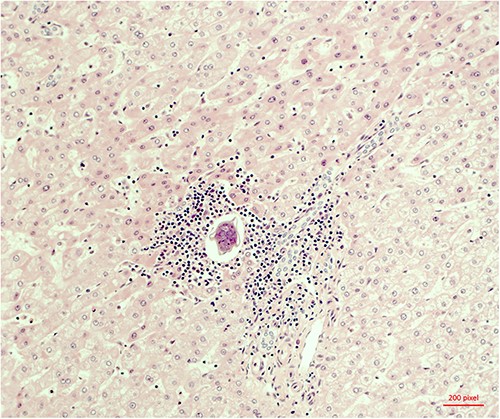

The histopathological work-up revealed the already described macroscopic cystic lesion (Fig. 4). More precisely, a pseudocyst, which differs from a cyst in that it does not possess an epithelial lining. Within the pseudocyst, necrotic liver parenchyma was found. In addition, and more surprisingly, parasites (Fig. 5) were found within the portal fields, partially within the blood vessels. These appeared to be schistosomas. It appeared that the necrosis within the pseudocyst was formed pursuant to ischemia. Finally, proof of schistosomiasis mansoni eggs in stool cultures was able to definitively render the diagnosis. An antihelmintic therapy with praziquantel was begun, under which the patient was able to completely recover.